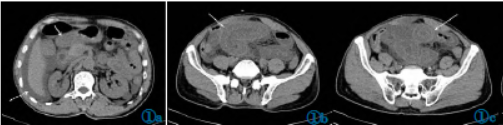

增强显示受累肠壁粘膜层及浆膜层明显强化,粘膜下层水肿并无明显强化,表现成“水靶征”,肠系膜动脉走行自然,未见充盈缺损(图2)。

图2AAPCT增强表现。图2a(横断位)、图2b(冠状位)、图2c(矢状位):腹部增强CT静脉期显示多处受累小肠壁粘膜、浆膜强化,粘膜下层水肿无强化,肠管横断位呈“水靶征”(图2a)(白色箭头所指),肠周积液无强化(图2a虚线箭头所指)。图2d(VRT图像)、图2e(MIP图像)、图2f(冠状位):腹部CTA显示肠系膜动脉走行自然,未见充盈缺损。